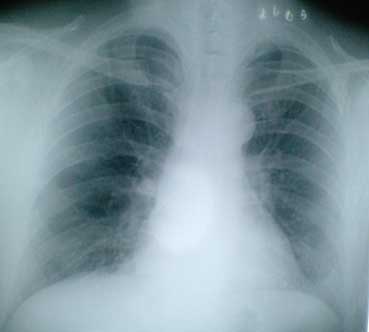

原因ははずかしくって言えませんが、息をしても痛い!クシャミをすると死ぬほど痛い!咳もまともにできない!状態で医者に行ったところ、肋骨骨折・ヒビは免れたようでひと安心。ただし、これからドンドンいたくなって1週間後が最も痛いと脅かされて帰ってきました。

しかし、上記のレントゲン写真。お願いして撮らしてもらったのですが、こんな写真撮って帰ったのは開院以来初めて!と言われました!

心臓に毛が生えているのは写っていませんでした。